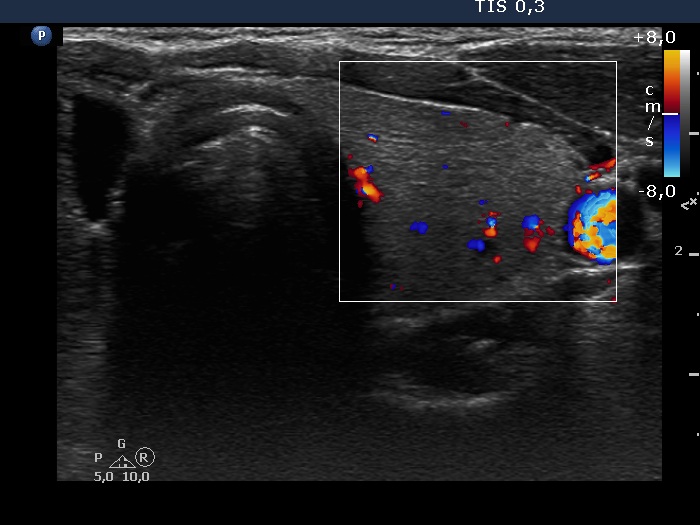

Left lobe, transverse scan, color Doppler mode. The vascularization is non-specific.